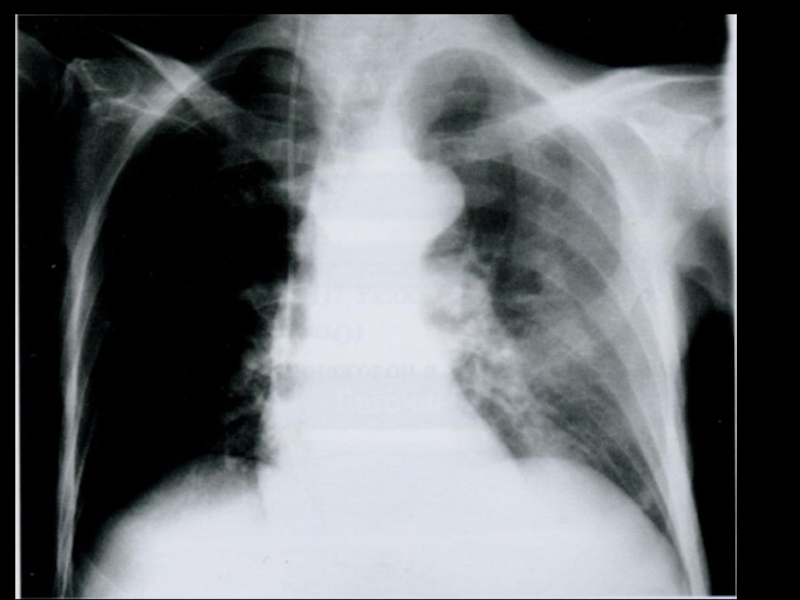

Слайд 6Рентген-диагностика АП

Обычно не бывает признаков смещения средостения в какую-либо сторону,

на

рентгенограммах можно обнаружить очаговые различия плотности легочного рисунка, которые связаны с развитием перибронхиальной экссудации.

иногда рентгенологическая картина напоминает таковую шокового лег­кого, но без расширения корней легких.